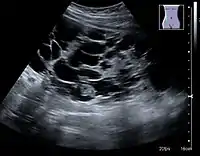

The kidney is divided into parenchyma and renal sinus. The renal sinus is hyperechoic and is composed of calyces, the renal pelvis, fat and the major intrarenal vessels. In the normal kidney, the urinary collecting system in the renal sinus is not visible, but it creates a heteroechoic appearance with the interposed fat and vessels. The parenchyma is more hypoechoic and homogenous and is divided into the outermost cortex and the innermost and slightly less echogenic medullary pyramids. Between the pyramids are the cortical infoldings, called columns of Bertin (Figure 1). In the pediatric patient, it is easier to differentiate the hypoechoic medullar pyramids from the more echogenic peripheral zone of the cortex in the parenchyma rim, as well as the columns of Bertin (Figure 2).[1]

Figure 1. Normal adult kidney. Measurement of kidney length on the US image is illustrated by ‘+’ and a dashed line. *Column of Bertin; ** pyramid; *** cortex; **** sinus.[1]